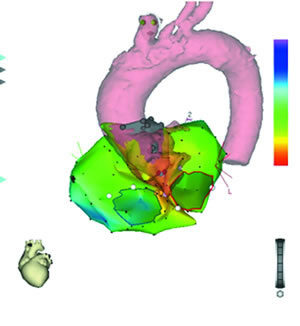

图3 右心房激动标测图 图4 左心房激动标测图 图5 主动脉根部激动标测图

图3:先行右心房三维重建及激动标测,见希氏束附近较大范围激动较早,右心房最早激动领先体表P波37 ms,单极标测局部呈rS型,试消融无效。

图4:左心房激动标测亦见前间隔区较大范围激动较早,左心房最早激动领先体表心电图49 ms,局部单极标测呈rS型,试消融无效。

图5:主动脉根部标测无冠窦激动最早,领先体表P波54 ms,单极标测呈QS型。

图6 CARTO激动标测多图融合显像

经电解剖标测和CT成像(CARTO-merge,图6)、主动脉根部造影(图7)证实,最早激动点位于无冠窦,在此处予以盐水灌注(35W,45℃)17ml/min,消融房速即刻终止(图8),猝发刺激及静脉滴注异丙肾上腺素未诱发任何心动过速。

图9 无冠窦与左房前间隔的关系 图10 无冠窦与右心房希氏束(黄色点)之间的关系

图11 CT显示无冠窦与左、右心房之间的关系, 百拇医药